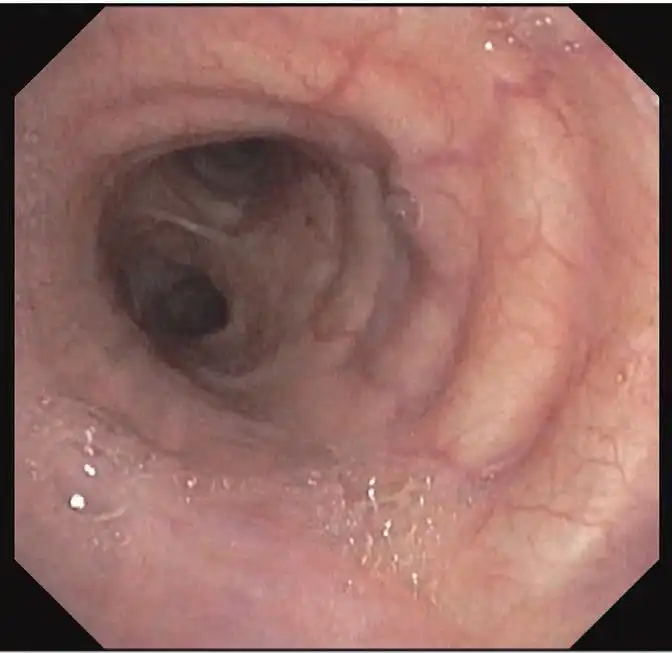

出色的图像质量

高分辨率的图像质量